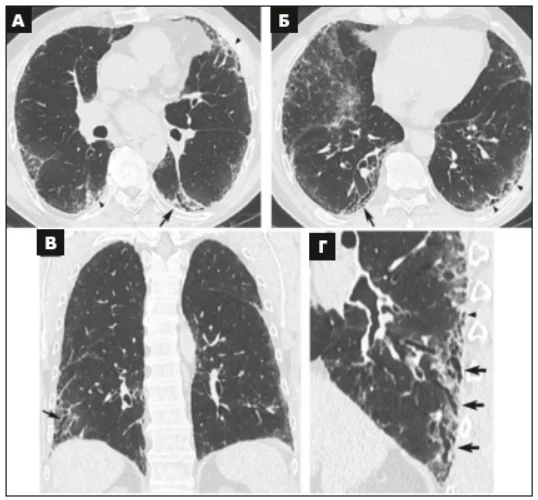

Виділено 4 діагностичні категорії, які складаються з КТ-симптомів (табл. 2 доповнена у 2022 р.). Ці категорії охоплюють ЗІП-патерн (рис. 1), імовірний ЗІП-патерн (рис. 2), невизначений (сумнівний) ЗІП-патерн (рис. 3) і альтернативний діагноз (рис. 4).

Рис. 1. КТВРЗ демонструє патерн ЗІП.

Поперечні (аксіальні) зрізи КT (А, Б, Г), корональна реконструкція (В), що показують наявність стільникових змін із субплевральним і базальним переважанням. Наявне м’яке ПМС (Г). Збільшене зображення лівої нижньої частки, на якому показані типові характеристики стільників, що складаються зі скупчень кістозних повітряних просторів із чітко окресленими стінками і варіабельним діаметром, видимі в одному або декількох шарах (стрілки) [3].